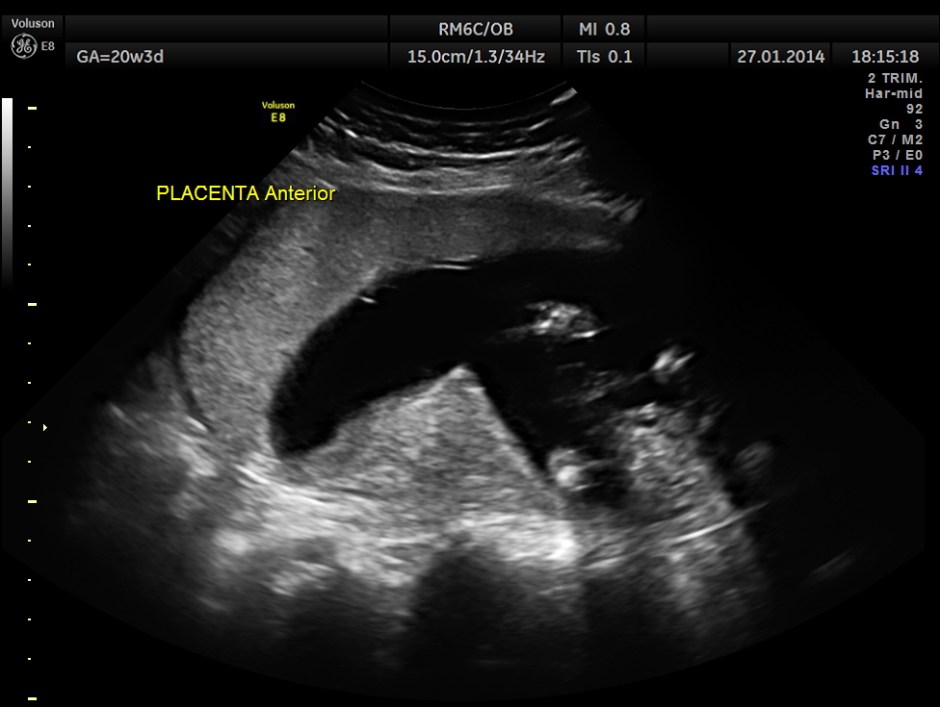

The GA was around 25 weeks , but the AUA was around 19 to 20 weeks. All parameters – BPD, HC, AC, FL are < 2.3 %tile and all other long bones are < 5.0 %tile.

Prominent placentomegaly seen .

Oligohydramnios seen.

Fetal kidneys are hyperechoic and enlarged.

Umbilical arterial P.I. and R.I. are higher for the GA.

At this point a diagnosis of Placentomegaly , Symmetrical Intra Uterine Growth Restriction , Probable renal dysplasia with oligohydramnios was suggested . The patient was referred by her consultant to a higher centre . The patient opted for termination of pregnancy as the 2nd opinion was also not favourable. But she had a spontaneous abortion few hours before the planned procedure. The fetus and the placenta underwent autopsy . The findings are summarised below :